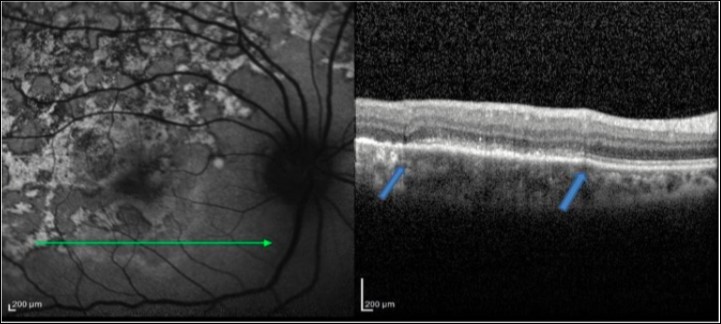

Figure 4.FAF (left) and corresponding eye-tracked SD-OCT image (right) of patient 1 healed stage of the left eye shows showed loss of RPE, POST, IS/OS junction, and ELM with increased reflectance from the choroidal layers. absent of the choroidal and intraretinal cells.

3. As the lesions healed further over the next 3–6 months, they appeared stippled with predominantly hypoautofluorescence. The SD-OCT scan showed loss of RPE, POST, IS/OS junction, and ELM with absent of the choroidal and intraretinal cells. The increased reflectance from the choroid persisted.